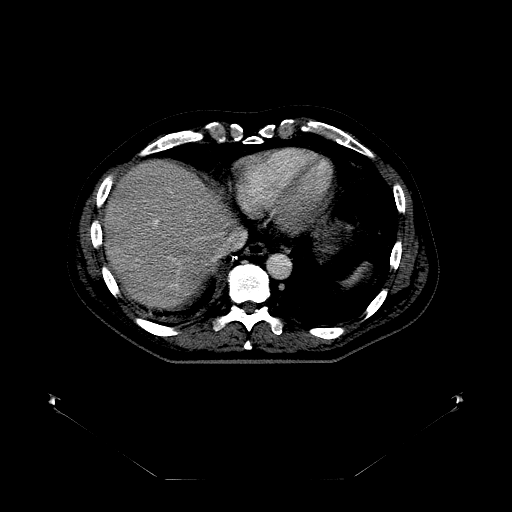

Case Study 3: Multi-Organ Segmentation

The cognition of artificial intelligence is important for computer-aided diagnostic. Multi-organ segmentation can help the machine understand the structure of the human body, which is very important for all the relevant tasks. Therefore, some research has focused on single- or multi-organ segmentation tasks, such as the liver([79, 80]) and the pancreas([81, 82]). In this case study, we use a VNet-based neural network to solve the multi-organ segmentation challenge, SegTHOR, [83]. The SegTHOR challenge includes about 40 CT images of the chest, and aims at the segmentation tasks of the heart, aorta, trachea, esophagus, and further more.

VI-1 Workflow and Implementation

As Fig. 11 shows, The workflow of this case study includes six parts: “input”, “pre-processing”, “dataset management”, “neural network”, “visualization”, and “analysis”. The “input” includes images of the chest and annotations.

“Pre-processing” rescales the range of the image values with a window width and a window level. Then, the input images are re-sampled with the “resample” tool to change their size. The “dataset management” function subsequently splits the dataset into a training and a testing set randomly, yet reproducibly.

“Neural network” employs VNet to train and validate the model, which can be used to segment organs from the chest. Then, the segmented images can be visualized via the “organ visualization” option, and the results can be analyzed with the “result analysis” tool to generate an MS-Excel based report.

VI-3 Result and Visualization